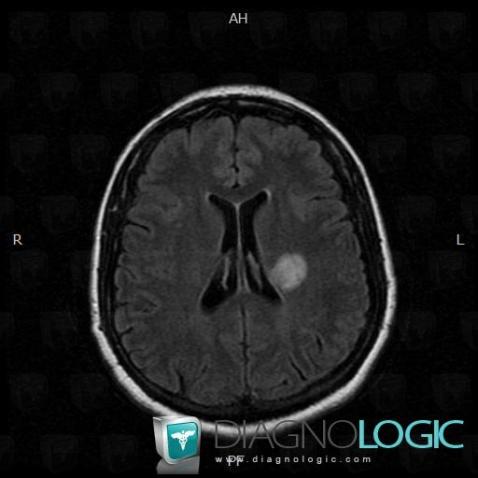

Multiple sclerosis, Cerebral hemispheres, MRI

Here is the specific information in the key image above:

- Diagnosis Multiple sclerosis, Location(s) Cerebral hemispheres, with gamuts DWI hyperintense lesion